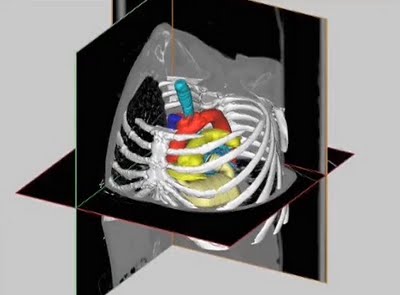

Biomedical Solutions Materialise

We ran across an interesting video that talks about Materialise’s ventures into the medical manufacturing space. We’ve posted about medical uses of 3D print tech before, but Materialise specializes in this niche, and have for quite some time. Materialise produces 3D software specifically designed for this market: Mimics, which can transform medical 2D CT or… Continue reading Biomedical Solutions Materialise